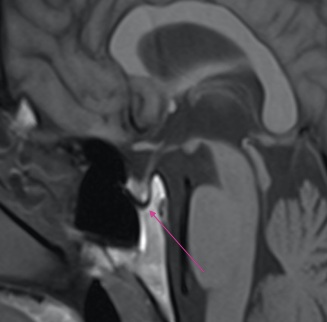

What is indicated by the arrow?

Sella turcica